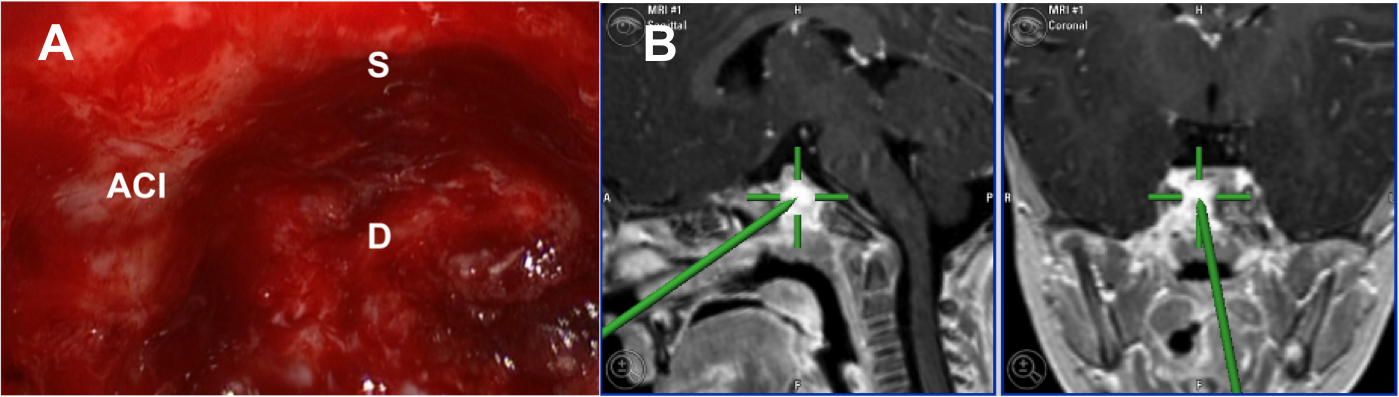

Introducción: La cirugía endoscópica endonasal se ha convertido en una herramienta fundamental para el manejo de patologías que comprometen la base de cráneo. En casos bien seleccionados, estas técnicas permiten resecciones quirúrgicas con una menor morbilidad sin comprometer los principios oncológicos de resección. Con el desarrollo de instrumental especializado, nuevas tecnologías y la experiencia de los cirujanos, la cirugía endoscópica endonasal se usa cada vez más en cirugía de base de cráneo en niños.

Diseño: Estudio observacional descriptivo de tipo serie de casos. Metodología: se describe la experiencia con pacientes pediátricos llevados a cirugía endoscópica endonasal para manejo de tumores de base de cráneo en el Instituto Nacional de Cancerología entre julio de 2014 y diciembre de 2016.

Resultados: Fueron intervenidos 8 pacientes entre los 2 y 14 años, con una edad promedio de nueve años y un seguimiento promedio de 16 meses. En el 75% se hizo una resección total del tumor. Un paciente requirió una reintervención y un paciente fue sometido a radiocirugía post-operatoria. 1 paciente falleció a pesar de múltiples intervenciones, quimioterapia y radioterapia.

Conclusión: La cirugía endoscópica endonasal para tumores de base de cráneo puede ser utilizada de forma segura en los pacientes pediátricos, es una técnica que en casos bien seleccionados pueden ofrecer excelentes resultados disminuyendo la morbilidad y complicaciones de las técnicas abiertas.